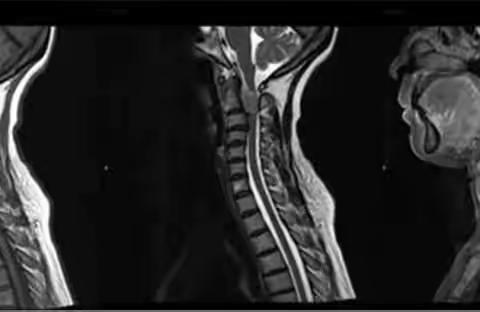

颈椎骨巨细胞瘤

颈椎脊膜瘤